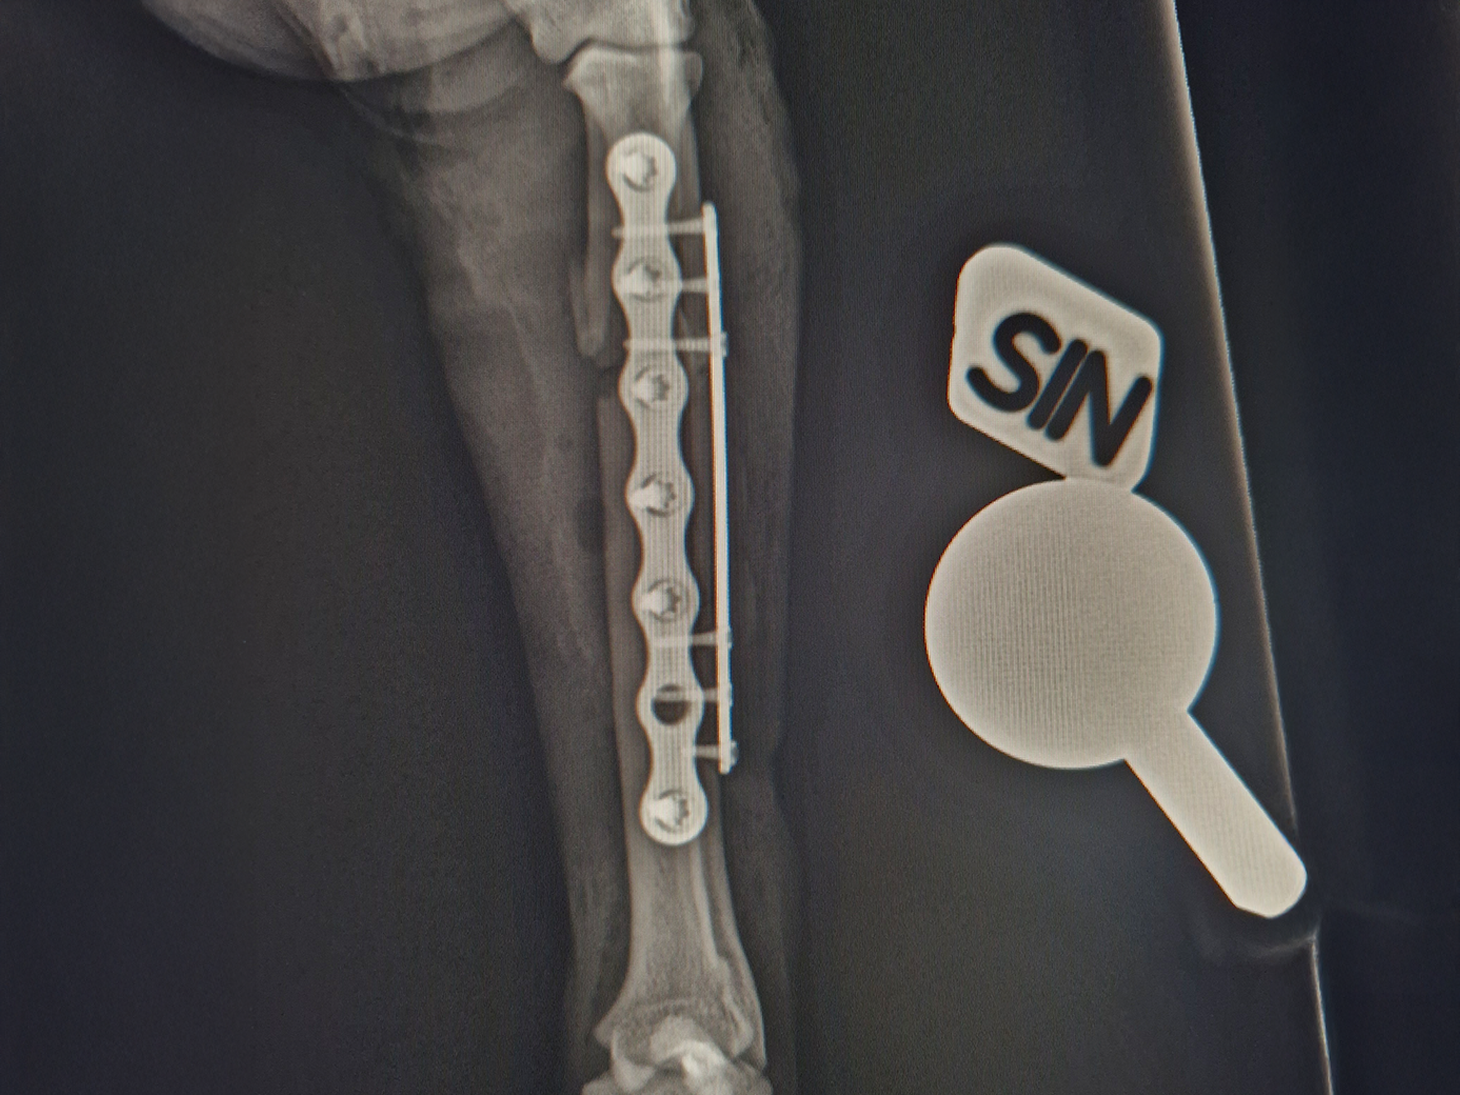

- The severely comminuted radius fracture was stabilized using a 2.0 mm titanium LeiLOX plate, specifically chosen to manage the comminution in combination with a supportive repair of the ulna.

- The ulna fracture was addressed with our innovative 1.0 mm titanium LeiLOX plate, secured by 1.3 mm locking screws. This combination provided robust, yet minimally disruptive, fixation crucial for a small patient. The surgical site was thoroughly flushed, and the patient received Cefazolin both perioperatively and for three days post-op to manage the open wound.

- X-Ray Confirmation: The surgery sites were fully healed, with no discomfort upon palpation. X-rays showed advanced healing with significant callus formation and all implants intact.

This case is a powerful example of how the entire LeiLOX system, including the new 1.0 mm plate, provides the secure, tissue-friendly stability needed for complex fractures. It allows for highly specific and robust stabilization in small animal orthopedics, enabling a rapid and complete return to function, even in highly active patients. It is inspiring to see this technology fully restore the beloved family member's mobility and quality of life!